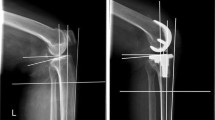

All components were well fixed according to radiographic evaluations during the postoperative follow-up. In this study, we chose exact postoperative anteroposterior (AP) and lateral radiographs and full-length AP radiographs. Mechanical axes of each extremity were defined by straight lines drawn based on Sikorski’s and Vanlommel’s descriptions [33, 36]. The mechanical femoral and tibia angle was measured accordingly. The mechanical axis of femur between the centre of the femoral head and the middle of the intercondylar region and the mechanical axis of tibia between the centre of the tibial component surface and the centre of the talus were made, and the mechanical femoral and tibia angle represents the angle between the mechanical axis of femur and the mechanical axis of tibia (Fig. 1a). Mechanical axis of limb was defined by a straight line drawn from the centres of the femoral head to the centre of the talus. The weight-bearing ratio was calculated by measuring the distance from the medial edge of the proximal tibia to the point where the mechanical axis of limb intersects the proximal tibia, and then dividing that measurement by the entire width of the proximal tibia. A percentage was calculated by multiplying this ratio by 100 % (Fig. 1b).

Mechanical femoral–tibial angle and weight-bearing ratio. a Mechanical axis of femur, tibia, and limb were defined by the use of full-length AP radiographs. The mechanical femoral tibial angle represents the angle between mechanical axis of femur and tibia. b The location where the mechanical axis of limb intersects the tibial component is expressed as a percentage of tibia with (weight-bearing ratio = a/b × 100 %)

These 30 patients were divided into 2 groups according to a discriminatory threshold of 40 % weight-bearing ratio: nine knees were in the varus alignment group (weight-bearing ratio 28.5 ± 10.3 %) (mechanical femoral and tibia angle 184.4° ± 1.5°), and 21 knees were in the normal alignment group (weight-bearing ratio 55.0 ± 7.0 %) (mechanical femoral and tibia angle 178.8° ± 1.8°).